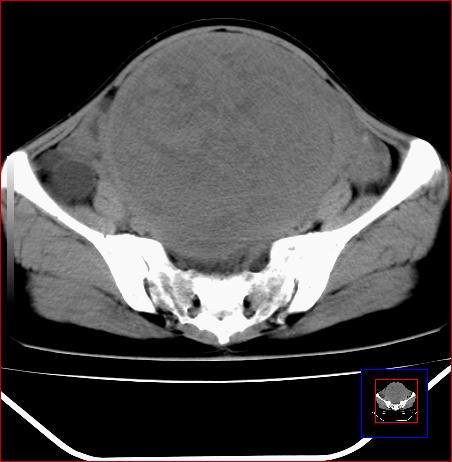

标题: CT15141:子宫肌瘤还是卵巢肿瘤 [打印本页]

标题: CT15141:子宫肌瘤还是卵巢肿瘤

腹部包块1年余,近两月明显增大,月经量多

病灶呈实性包块,边界清晰,似与子宫分界不清,考虑:子宫肌瘤

病灶呈实性包块,边界清晰,似与子宫分界不清,密度低于肌肉,考虑:恶性可能,确诊需要妇科诊刮。

子宫体积增大,内密度不均匀。边缘清晰。考虑子宫肌瘤。

子宫体积增大,内密度不均匀。边缘清晰。考虑子宫肌瘤可能性大。